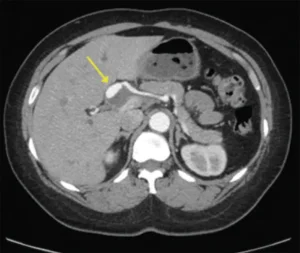

Thông thường, chẩn đoán được thực hiện thông qua một hoặc nhiều phương pháp hình ảnh. Do thiếu triệu chứng đặc hiệu của phình động mạch gan, việc chẩn đoán lâm sàng mà không có hình ảnh có thể gặp khó khăn.

- Chụp cắt lớp vi tính (CT): Một loạt các hình ảnh X-quang được chụp từ các góc khác nhau của cơ thể, tạo ra hình ảnh chi tiết về các cơ quan, mô hoặc xương. Quá trình chụp CT mất khoảng 10–20 phút để hoàn thành.